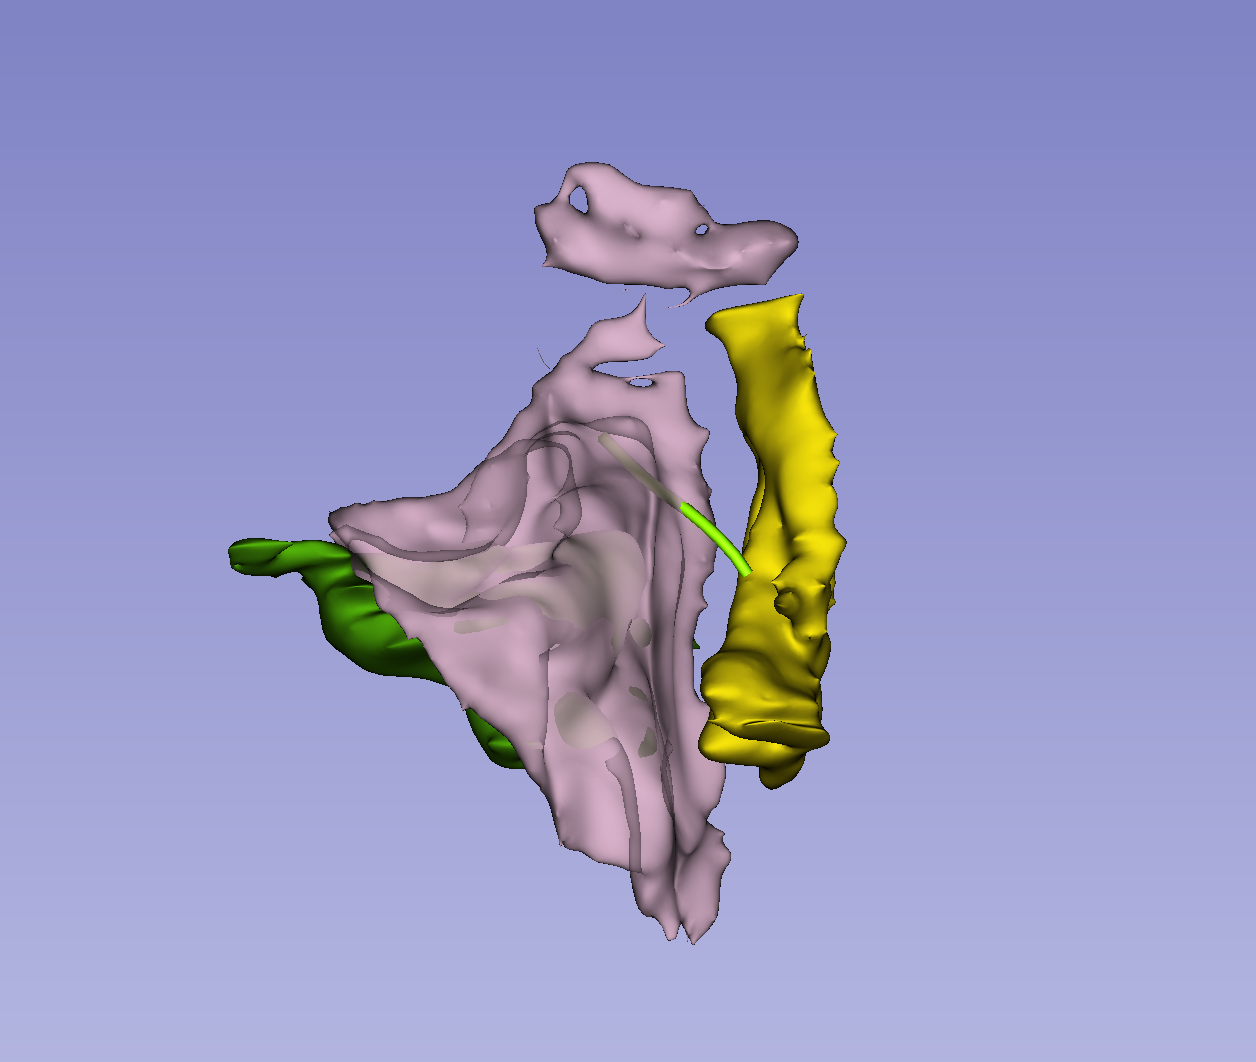

Quantitative Analysis of Human Orbitofrontal-subgenual Circuitry

The orbitofrontal-subgenual circuitry is important for the treatment of major depressive disorder (MDD) using non-invasive treatments in psychiatry, such as transcranial magnetic stimulation (TMS) or invasive neurosurgical approaches such as Deep Brain Stimulation (DBS). The anatomical structures involved in this circuitry are the orbitofrontal cortex, Brodmann’s area 11(BA 11), the Subcallosal area, BA 25 and the fiber tract that interconnects these two cortical areas, namely the frontopolar bundle. The two cortical areas of this circuitry can be targets for TMS procedures or DBS interventions.

- We will segment the orbitofrontal cortex and the subcallosal area using SLICER in the individual subject brain using T1 MRI data.

- We will connect these two cortical regions using the tractographic white matter query language (WMQL) software on diffusion MRI data of the same subject.

- Segmentation of orbitofrontal cortex and subcallosal area successfully performed on T1 data.

- Whole brain DMRI tractography successfully performed.

- Diffusion and Structural data registered.

- WMQL query performed.

Illustrations